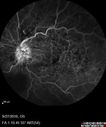

74 year old female - Over the last 4-5 weeks the vision in the left eye has been declining. The vision has been a little clearer the last week. Prior to this episode the vision in the left eye was pretty good. She had an MVA August 6 and was hit and spun around 3 times then hit an oak tree. The vision in the right eye. Vision 20/32 OD 20/100-2 OS - OS vision improved to 20/32 after 5 injections (monthly) of avastin

Hemicentral Vein Occlusion Left Eye531 viewsVision improved from 20/100 - 2 to 20/32 with 5 monthly Avastin treatments.00000